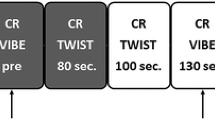

The developed AP

Our evaluative process led to the following 4 acquisitions for the AP: T2, T1-pre prior to contrast, and post-contrast T11.5, and T16 (necessary for kinetic curve calculation). Maintaining T2 as the first acquisition would preclude efficiency of the AP. Therefore, this acquisition, unaffected by contrast, can be placed in the time gap between T11.5 and T16 as the final step in the development of the AP (Fig. 2). This reduces scan time from 24 to 7.5 min. Using such an AP, all 7 malignancies and 10 suspicious benign lesions would have been identified. For institutions using T15 verses T16 for evaluating kinetic activity, scan time would be 6.5 min.

The subscript of the T1 acquisitions represents the time in minutes post-injection. For the FDP, the first post-injection acquisition (T11) starts 35 s after initiation of the injection. For the RP, the first post-injection acquisition (T11.5) starts 65 s after initiation of the injection

Reduction of full diagnostic protocol (FDP) to rapid protocol (RP).